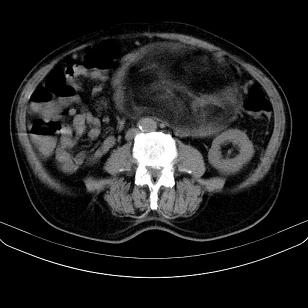

标题: CT21671:男,88岁,左上腹包块 [打印本页]

标题: CT21671:男,88岁,左上腹包块

患者因咳嗽而住院,自觉右上腹包块,无其他不适。

腹膜后高分化脂肪肉瘤

腹膜后脂肪肉瘤

腹膜生占位性病变,脂肪肉瘤可能。

支持;后腹膜脂肪肉瘤诊断。

另肠腔扩张及液平,肠梗阻?